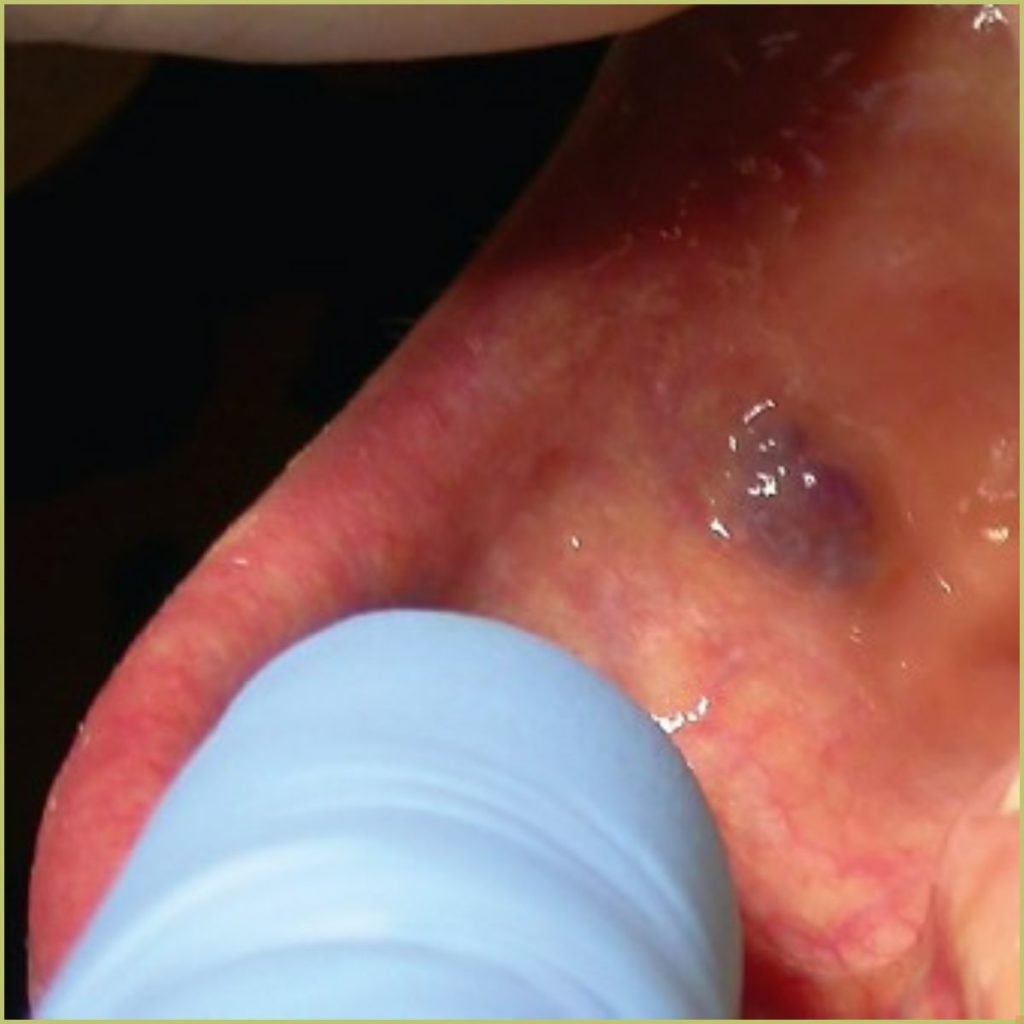

ECCHYMOSIS

Ecchymosis is the medical term for a larger-than-pinpoint bruise caused by soft tissue hemorrhage. Though trauma is the most common cause, ecchymosis can be caused by many conditions that affect bleeding including severe infection, malignancy, blood dyscrasia, thrombocytopenia, and hemophilia. Any vascular wall defects or coagulopathy will lead to excessive bruising. The common clinical presentation includes:

- Nonvesicular, macular surface.

- Does not blanch when pressure is applied.

- Can appear red, reddish-blue, or brown depending on extent and maturity.

Diagnosis is usually based on the lesion history and clinical presentation alone. A blood count and coagulation profile is often required to get to the root cause of the problem. Your differential diagnosis should include:

- Hemophilia.

- Kaposi’s sarcoma.

- Hemangioma.

- Thrombocytopenia.

- von Willebrand’s disease.

- Leukemia.

- Trauma.

Treatment involves addressing the etiology.